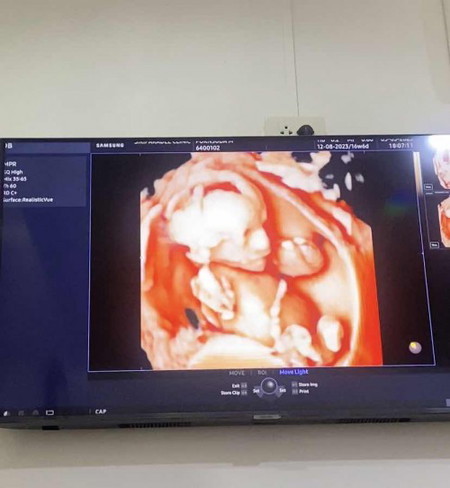

ยินดีด้วยค่ะคุณได้ลูกชาย👦🏻

ตั้งชื่อไว้เล่นๆว่า “น้องพอใจ” แต่ผลนิฟออกมาต้องพับชื่อนี้ไปก่อน เพราะผมเป็นเด็กชายค้าบแม่แม่555555 #ลูกชายคนแรก #18_Weeks